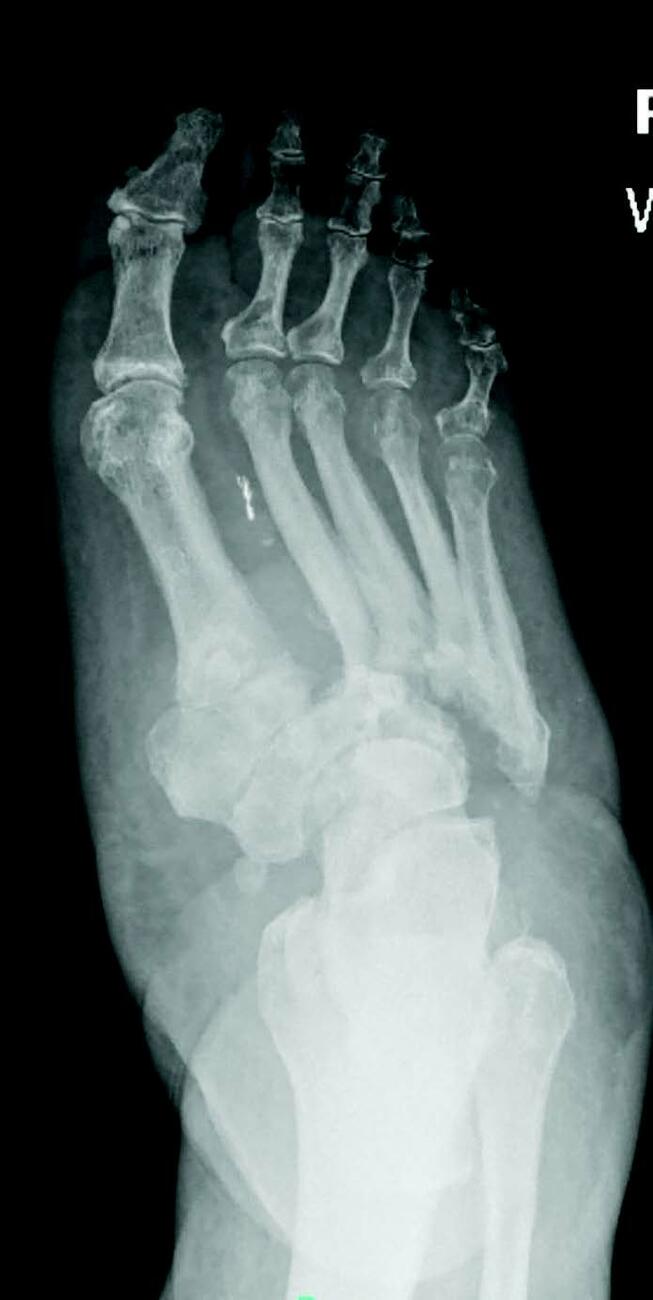

Charcot neuroarthropathy is a tissue-destructive process of the musculoskeletal system in patients with neuropathy.6-9 Most commonly affecting the foot and ankle, Charcot develops from repetitive trauma to an insensate foot. Historically, two theories describe the etiology of Charcot neuroarthropathy: the neurovascular theory; and the neurotraumatic theory. The neurovascular theory proposes that altered autonomics in patients with neuropathy leads to arteriovenous shunting and increased arterial flow, precipitating amplified osteoclastic activity and subsequent bone resorption and fracturing.10-11 The neurotraumatic theory suggests unrecognized trauma in neuropathic patients leads to repetitive injury and subsequent breakdown.12

Regardless of the cause, an acute Charcot foot is a hyperinflammatory event in the setting of immune dysregulation. Jeffcoate and colleagues hypothesized that Charcot foot developed due to the release of pro-inflammatory cytokines in an amplified immunologic response to trauma.12 They proposed a post-traumatic pathway that resulted in increased expression of TNF-α and IL-1ϐ. These cytokines induce increased expression of RANKL, which activates NF-κϐ (a transcription factor), mobilizing osteoclasts for osteolysis. Such a process would be a healthy response to injury, but in the setting of neuropathy, the injured site may sustain repetitive insults. Perhaps these repetitive insults manifest immune dysregulation, leading to an uncontrolled hyperinflammatory state.12-13 There is limited research to support this elegant theory, but there is acceptance of the proposed pathway as the most likely mechanism driving Charcot collapse.

Uccioli and team found that the patient with acute Charcot exhibits an inflammatory monocyte phenotype compared to healthy controls with diabetes.8 They also found increased concentrations of circulating cytokines in patients with acute Charcot.14 Baumhauer and coworkers utilized immunohistochemistry methods to evaluate cytokine mediators of bone resorption in osseous specimens of patients with Charcot arthropathy.15 They found enhanced activity of osteoclasts in the setting of IL-1, IL-5, and TNF-α activity,15 which supports the pro-inflammatory hypothesis.12-15

Management of the acute Charcot foot involves management of any present ulceration or infection and aggressive offloading through immobilization to prevent progression of deformity and amplification of the inflammatory cycle.16-17 There is some early evidence to suggest using immunomodulators such as TNF-ɑ inhibitors in the management of acute Charcot foot.18 Bisphosphonates are occasionally part of the treatment for the acute Charcot foot with mixed results.19 Surgical management of the acute Charcot foot is rarely indicated as surgical trauma may worsen the inflammatory cascade, resulting in even more bone resorption.